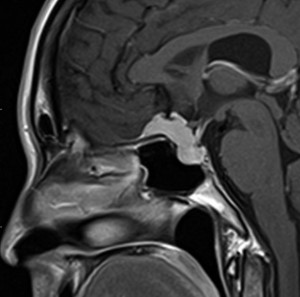

大脳鎌テント接合部髄膜腫 falcotentorial meningioma

30代の女性に発生した髄膜腫です,一見すると松果体細胞腫と見分けはつきません。右の画像に見られるように典型的な中脳水道狭窄を生じていました。

軽度の閉塞性水頭症もありますが,頭痛も無く無症状なので経過を観察しました。髄膜腫だと診断できるのは,右の画像で見られるようにガレン大静脈が右側に偏っているからです。松果体細胞腫の場合は,ガレン大静脈は上方に変位します。

1年間経過観察したら水頭症が進行して脳室が拡大,腫瘍のサイズも大きくなりました。右側の画像で見られるようにガレン大静脈の左側のテントの下面から発生した髄膜腫でした。

左は手術直後の画像です,手術は左側のテント下面を見るために,後頭部経テント法 OTA occipital transtentorial approach で,小脳テントの左側を切断して腫瘍を全摘出しました。右側は6年後の画像ですが,腫瘍再発はありません。

「注意」症状のない患者さんには,なかなか勧められないリスクの高い手術です。この患者さんの場合は無症状で水頭症も軽度で経過観察をしたのですが,本当はそうしてはならないものでした。閉塞性水頭症が急激に悪化して,急性水頭症のために意識障害になる可能性があるものです。